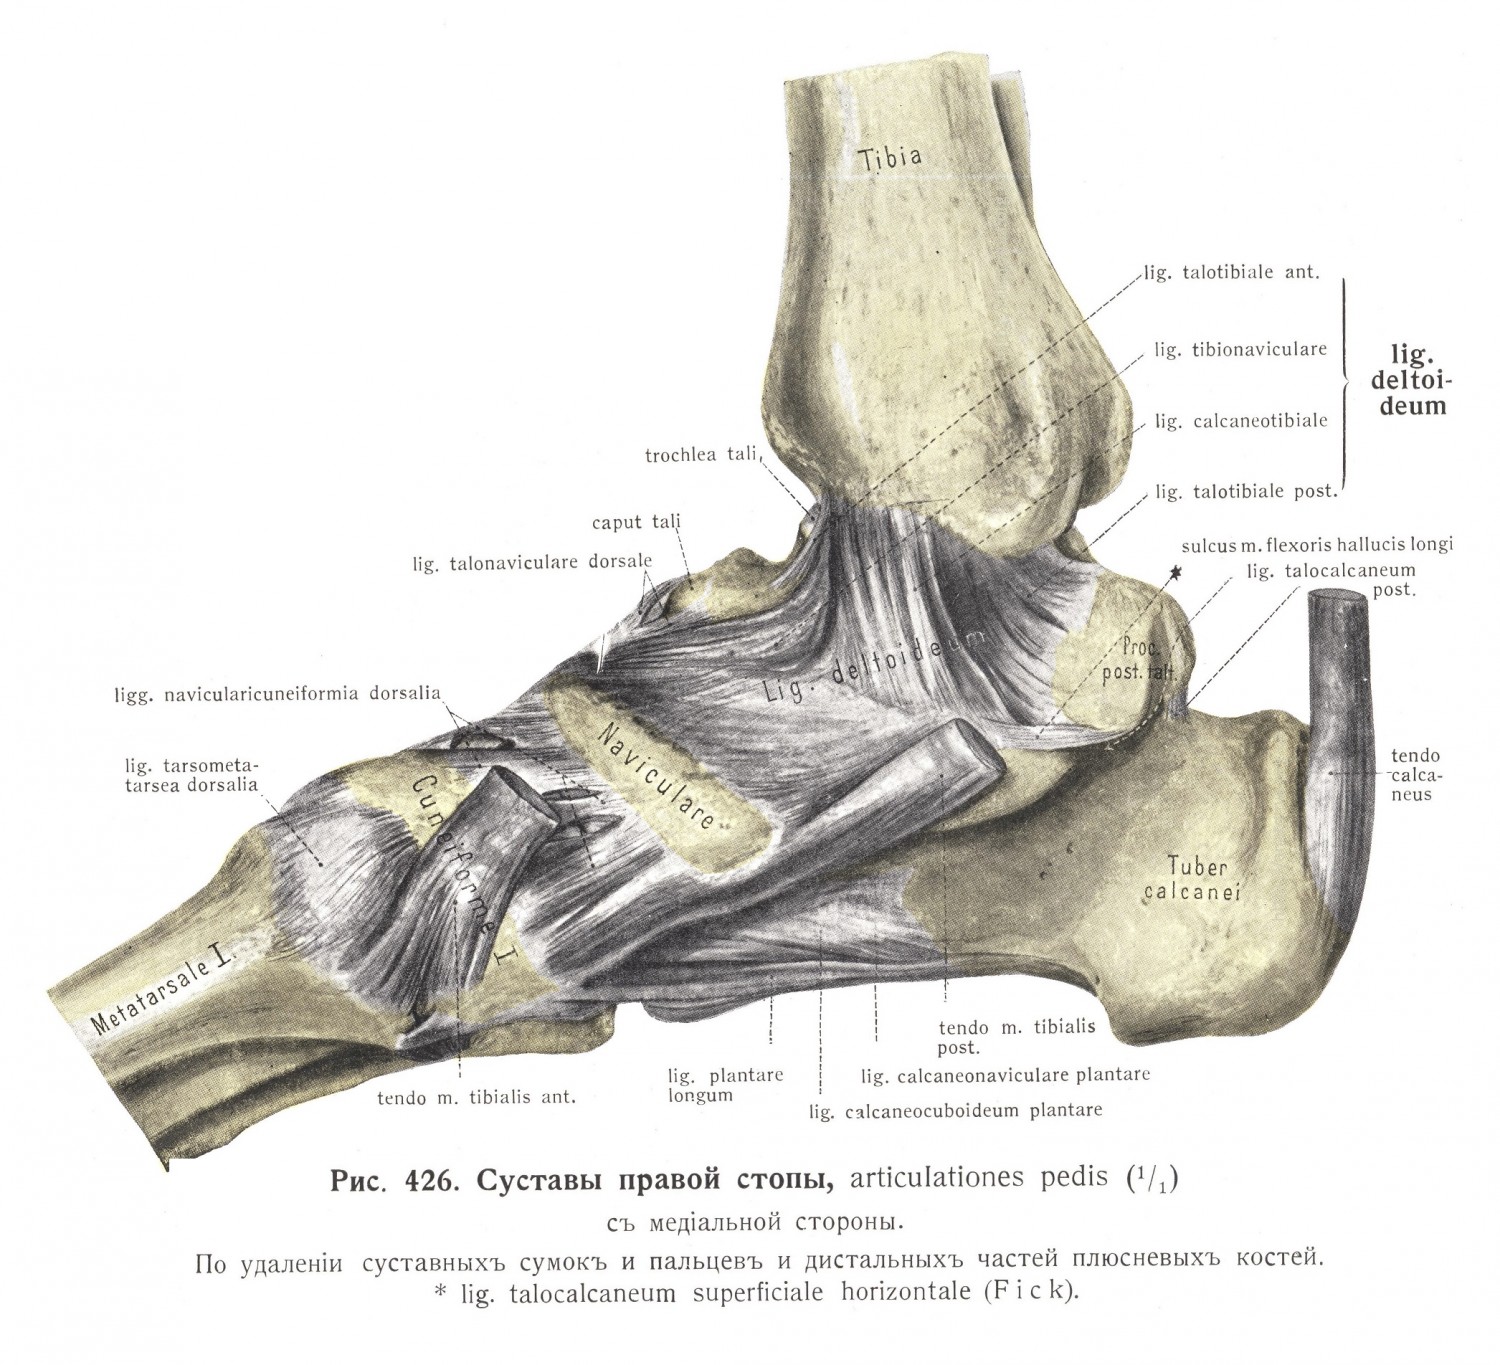

Анатомия суставов Шапарова и Лисфранка: фото и информация